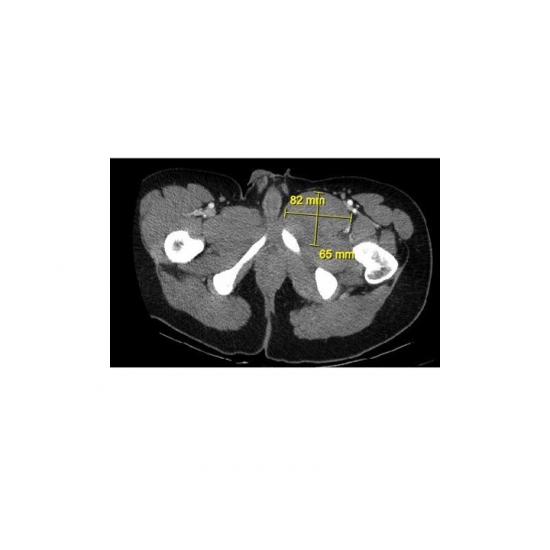

| Lethal Leg Pain - Page #3 | |||